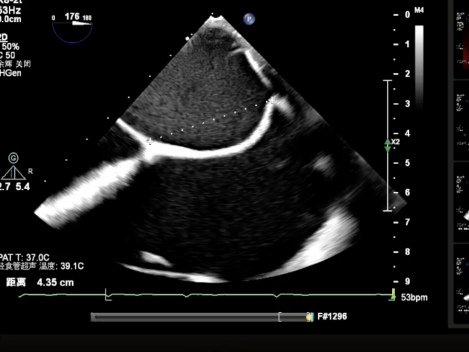

测量穿刺点距离二尖瓣环的位置,测量为4.35cm;沿着导丝置入可调弯导引导管,使其穿出穿刺点2cm左右